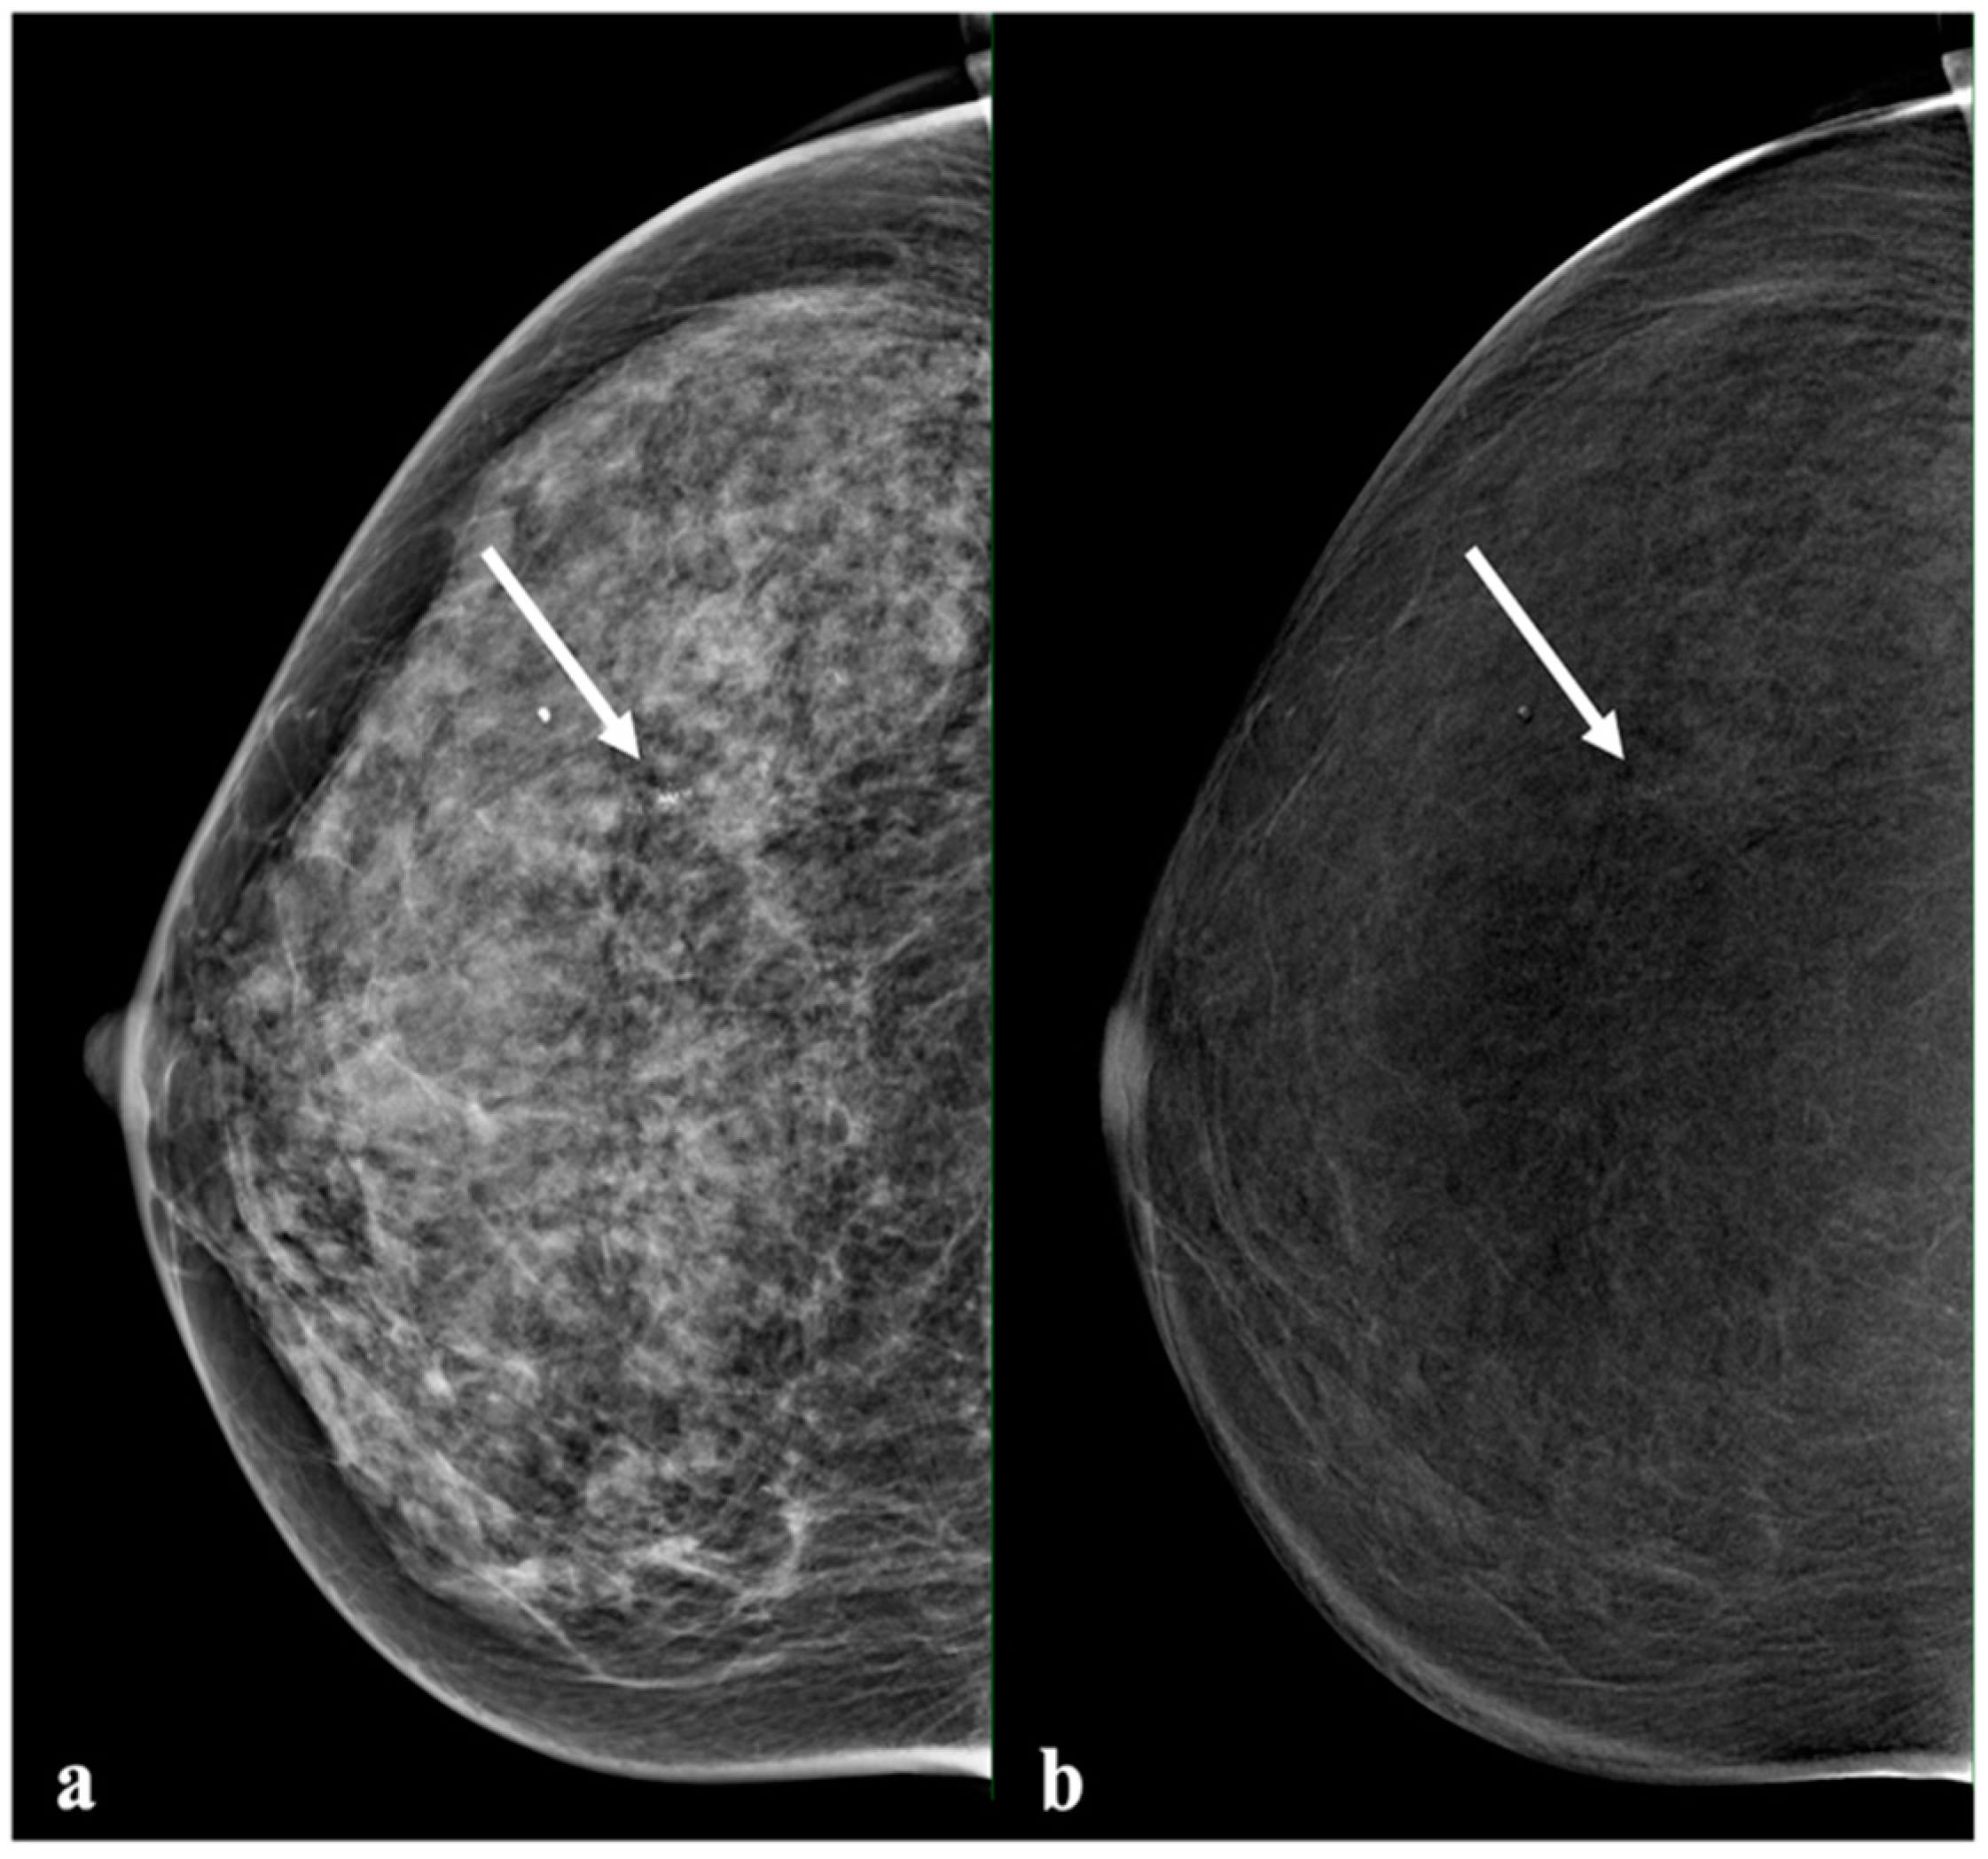

Figure 4.

Example of a lesion with no enhancement. A 55-year-old patient with a small group of suspicious calcifications in the right breast. Histology showed high-grade DCIS. Mammography ((a), low energy) showed a group of pleomorphic calcifications with a linear distribution (arrow). The recombined image (b) showed a mild background parenchymal enhancement and suspicious enhancement in the area with the calcifications (arrow).

In clinical practice, both FN cases of invasive cancer and DCIS manifested with suspicious microcalcifications and, therefore, were not missed on LE mammography and CEM.